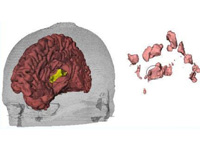

Integrative Visualization of Temporally Varying Medical Image Patterns

We present software for the visualization of temporal changes of disease patterns using stacks of medical images collected in time-series experiments. With this software users can generate 3D surface models representing disease patterns and observe changes over time in size, shape, and location of clinically significant image patterns. Statistical measurements of the volume of the observed disease patterns can also be obtained simultaneously.

Generation of Connectivity-Preserving Surface Models of Multiple Sclerosis Lesions

In this article we introduce a software tool to build 3D surface models of Multiple Sclerosis (MS) brain lesions from 2D image stacks typically obtained through Magnetic Resonance Imaging (MRI). This tool allows users to create 3D models of MS lesions quickly and visualize the lesions and brain tissue using various visual attributes and configurations.

A Novel MRI Visualization Tool for White Matter Pathology in Multiple Sclerosis

We developed a tool to visualize MS lesions and their 3D surface models to show changes in the lesions over time. These can be shown as an animation to elucidate differences across scanning sessions. With this software, a volumetric sub-region can be selected from the 3D model for zooming or animation, and a point on the 3D model can be selected to highlight all lesions connected to it. The total volume of lesions can be calculated, displayed as a chart, and exported.